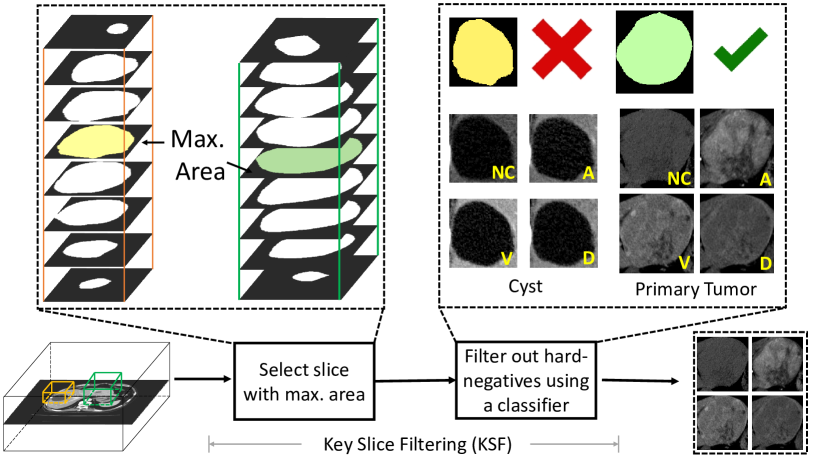

A fully automatic tumor characterization pipeline requires first finding the lesion(s) from the larger volume and then classifying them. Naturally, the 3D detector of Sec. II-A, trained using the data curated by Sec. II-B’s processes, can localize lesions. However, additional filtering is necessary to extract reliable tumor \acpROI. We present a dedicated \acfPTS module for this purpose, which is composed of the 3D CenterNet detector and a subsequent \acfKSF process.

The first step of \acPTS is to apply the 3D CenterNet detection to generate primary lesion candidates. We train this implementation using public datasets [23, 22], our labeled dataset and the new harvested lesions in from Sec. II-B. From this detector, we extract up to high-scoring 3D bounding boxes per volume. One or more of these candidates ideally overlap with the primary lesion(s); whereas many likely overlap with false positives, e.g., blood vessels, or non-significant lesions, like cysts (Fig. 5). These undesirable candidates must be rejected.

For reasons that Sec. II-D will explain, and our subsequent results would support, the downstream tumor characterization procedure is performed on 2D tumor \acpROI across four \acCT phases. Thus, any lesion candidate filtering must both select key 2D slices and, from these, select the most likely one belonging to a primary tumor. We call this \acfKSF. As Fig. 5 illustrates, we perform \acKSF by first applying a binary lesion segmentation network, trained using , on each whole slice of the volume. Then for each 3D candidate, we choose the slice corresponding to the greatest prediction area as the key slice. While in principle any segmentation network can be incorporated, we choose to fine-tune the 2.5D segmentation head of the MULAN lesion detector [28]. We opt for this model for two reasons: (1) The segmentation head is pre-trained on DeepLesion [22] and should possess features with high lesion affinity; (2) the 2.5D segmentation allows us to incorporate sufficient background context without downsampling and compromising the CT resolution.

With key slices selected for the top 3D candidate proposals, \acKSF then separates them into primary and non-primary tumors. To do this, we apply a classifier on the multi-phase key slices (Fig. 5). Thanks to the data curation pipeline in Sec. II-B, we have ample true- and false-positive candidates to train such a classifier. In this way, the data curation and \acKSF steps can be viewed as hard-negative mining and hard-negative filtering, respectively. Any high-performing classifier can be used for this step, e.g., well-established appearance based \acpCNN or even the texture-based classifier we outline next in Sec. II-D. Next, for the tumors that are classified as primary, the corresponding detection scores will be used to break the ties, where the one with the largest detection score will be used as the primary tumor for the following Sec. II-D.